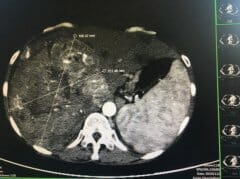

乙肝患者:早发现早治疗与肝癌“绝交”

肝脏是个沉默的器官,早期症状不明显,不易被发现。即使发现身患乙肝,很多患者仍不以为意,久拖不治从而错过最佳治疗时机。这也是肝癌治愈率低、死亡率高的一个重要原因。 肝癌与慢性肝病有关及早发现可防微杜渐 近日,60多岁的李女士到徐州市传染病医院就...

发现感染乙肝病毒后,定期复查的重要性

案例 :一位女性患者,45岁,在去年初就感觉右上腹部不舒服,有时候隐隐作痛,全身稍微有点乏力,自己以为是这几天熬夜、劳累造成的,所以没有在意,就这样坚持了一两个月,感觉右上腹疼痛加重了。她才去医院就诊,经过详细检查,她是一名乙型病毒性肝炎患者...

“肝癌”是怎么回事?和乙肝病毒相关?听听医生怎么说

今天我们要讨论的话题呢,是跟肝脏的终极疾病有关,也就是说最严重的肝脏疾...